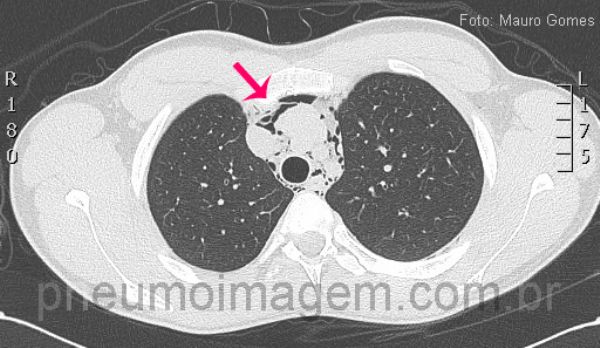

Corte tomográfico ao nível da traquéia demonstra a presença de ar dissecando as estruturas mediastinais e vasculares (seta vermelha). No pneumomediastino espontâneo não há evidências de traumatismo, iatrogenia ou pneumopatias prévias. Por se tratar de uma afecção incomum, eventualmente o diagnóstico não é feito, o que pode trazer consequências danosas e até mesmo fatais para o paciente.

CT slice at the level of the trachea demonstrating the presence of air dissecting mediastinal and vascular structures (red arrows). In spontaneous pneumomediastinum there is no evidence of trauma, iatrogenic or prior pulmonary diseases. It is an uncommon condition and diagnosis can be delayed and may have consequences harmful and even fatal to the patient.